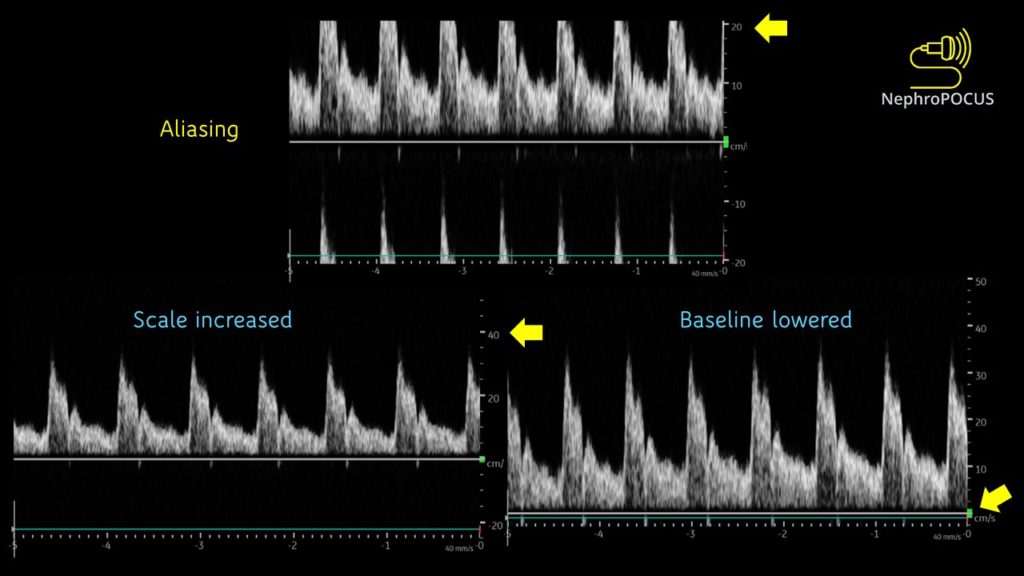

Aliasing

This is an important characteristic of PW Doppler that you need to be aware of. As the same transducer element is used to send and receive ultrasound pulses (= cannot listen continuously), there is a limit on the maximum velocity that can be detected. Particularly happens with deeper structures (= returning echoes take longer and the transducer is in the process of sending out next pulse before the previous echoes return completely – flow direction will be misread by the machine). When this happens, top portions of the waves are chopped off and displayed on the opposite side of the baseline. This is called aliasing [Figure 6]. This can be overcome by (1) increasing the scale [= PRF] and/ (2) lowering the baseline. Figure 7 illustrates how aliasing disappears by doing these two things. If nothing helps (e.g. velocity is too high), switch to CW Doppler.